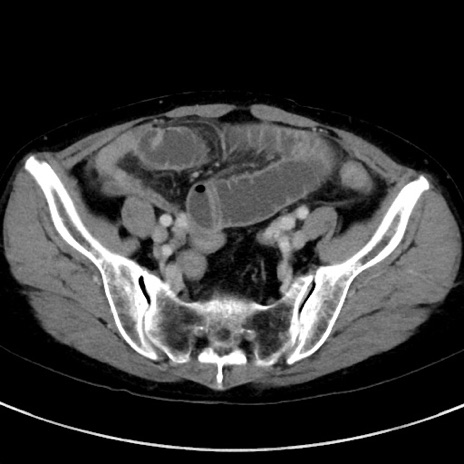

症例23(横断像)

【症例】70歳代女性

【主訴】下腹部痛・嘔吐

【現病歴】2日前より腹痛あり。昨日嘔吐あり。症状改善しないため来院。

【既往歴】胃GISTに対して胃部分切除後。

【身体所見】BT 37.1℃、BP 128/77mmHg、腹部:平坦・軟、下腹部に圧痛あり。

【データ】WBC 10200、CRP 0.31